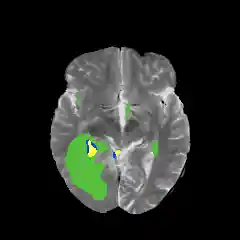

I tried out several different methods for sampling patches, which had a large impact on the results. I began randomly selecting patches of a given class from the data and repeating this for all five classes. However, with this sampling method approximately half of the background patches were just the zero-intensity area with no brain, so the model classified most patches with brain tissue as tumor, and only the black areas as background (Figure 9).

Figure 9: (Left) results of segmentation without excluding exclusively zero-intensity patches. Notice that even healthy tissue is classified as tumor. (Right) results of segmentation after restricting the amount of zero-intensity pixels allowed in a given patch. The tumor prediction is now restricted mostly to the actual area of the lesionI then restricted the selection process to exclude patches in which more than 25% of the pixels were of zero-intensity. This greatly improved the results, one of which can be seen on the right in Figure 9.